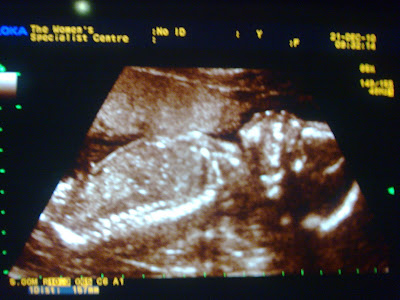

The latest picture of mei mei taken yesterday during her detailed scan. (Essentially, a regular scan with the doc carefully looks at the heart, lungs, brain, etc. He said everything looks fine).